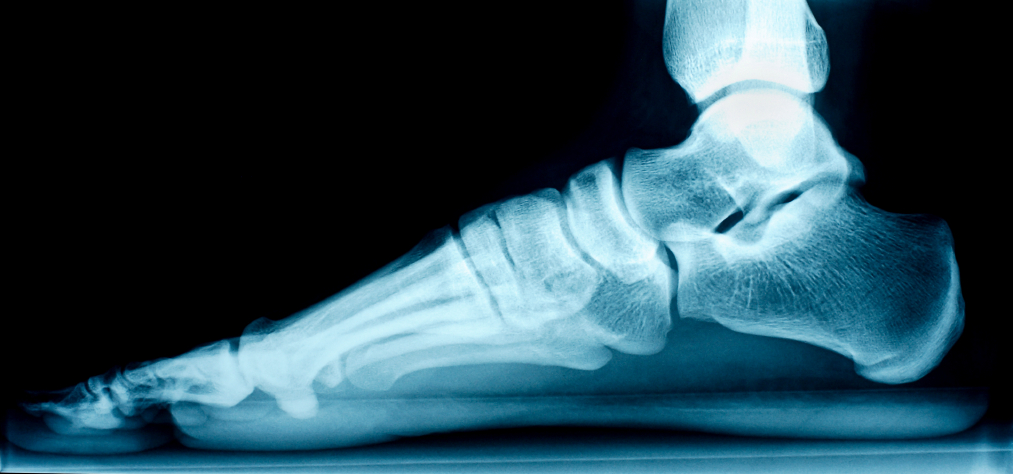

Stem cell therapy can be used for treatment of arthritis, ligament injuries, tendonitis, back  pain, knee pain, hip pain, shoulder pain, elbow pain, whiplash injuries, tennis elbow, rotator  cuff disease, patellar tendinitis, Achillies tendinitis, biceps tendinitis, plantar fasciitis, degenerative disc disease, spinal stenosis, and many other conditions.